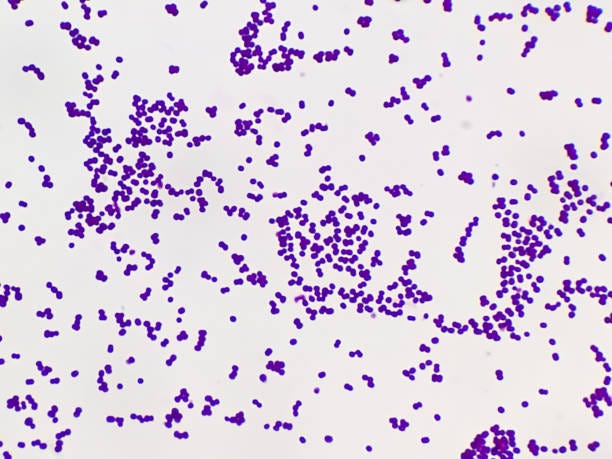

• S. pyogenes comprises non-motile and non-sporing cocci (round cells) that tend to link in chains.

• It is Gram-positive, meaning it has a thick peptidoglycan layer in its cell wall that retains the purple stain in the Gram staining procedure.